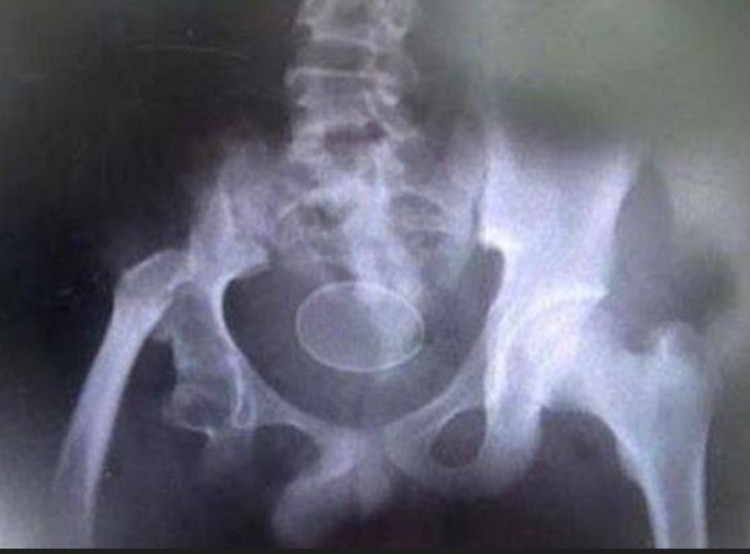

O garoto tinha dificuldade em andar quando chegou ao local e os médicos afirmaram ser impossível um humano colocar um ovo, mas a família de Akmal tinha um raio-x para comprovar a história.